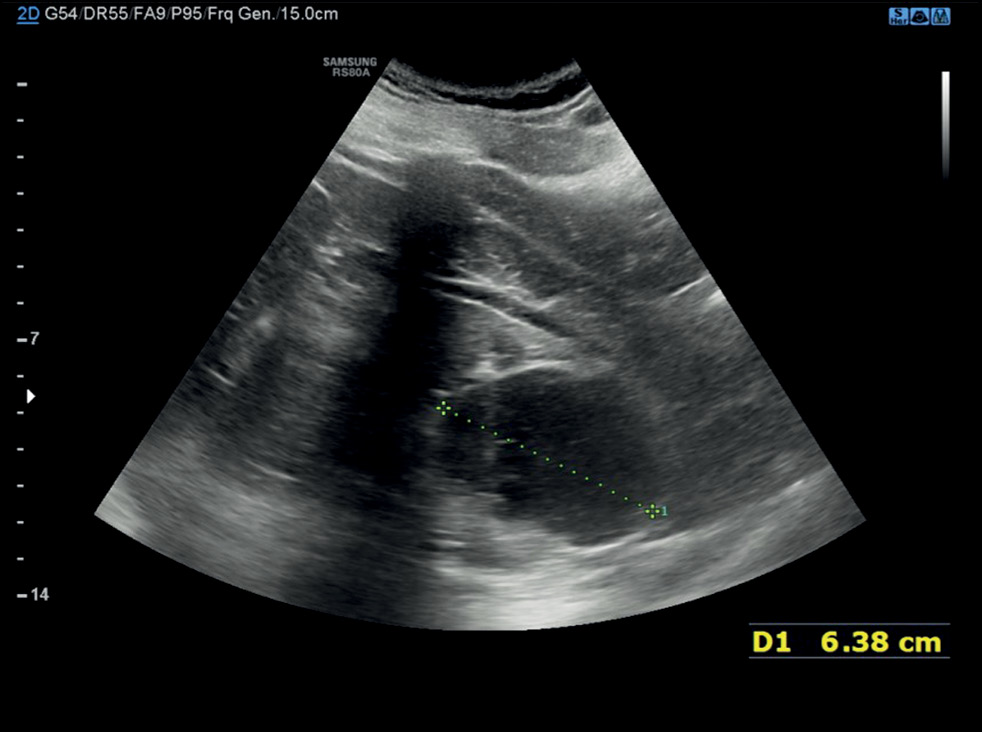

自发性肝破裂病例及影像学的作用:从计算机断层扫描到干预治疗

肝实质破裂是一种罕见但可能致命的疾病,可由外伤、医源性因素、自发性原因等引起。 本文通过一个病例报告,介绍了在治疗一名自发性肝实质破裂患者时所采用的诊断和治疗措施。一名老年妇女因弥漫性腹痛被送入急诊科。临床检查后,她接受了计算机断层扫描。第一次计算机断层扫描的结果并未发现全面的实质破裂。由于腹痛可能由肾绞痛或胆绞痛引起,已知信息模糊,因此早期诊断非常困难。在肝实质中只发现了几个椭圆形低密度肿块,肿块内充满了密度增高的液体。然而,疼痛持续了数天,由于患者病情恶化,进行了补充的放射检查,结果显示肝实质破裂。因此有必要进一步进行动脉造影,并延长住院时间,直到临床症状缓解。